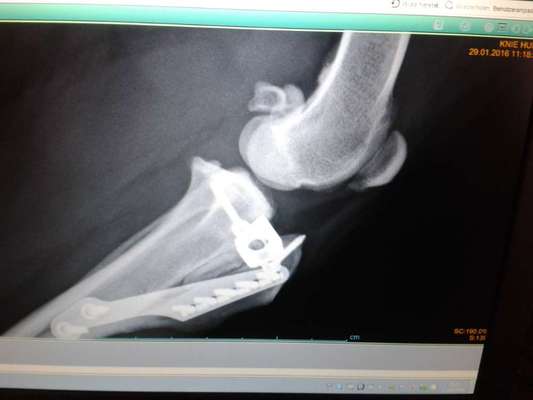

Hallo ihr Lieben, ich habe eine Hündin, 5 Jahre, 17 kg. Sie humpelt bei Überlastung. Bisher wurde es nach kurzer Zeit immer wieder gut oder mit Gang zum Tierarzt und Medikamenten. Geschont wurde immer danach und auch normal darauf geachtet, dass es gar nicht erst zu Überlastung kommt. Nun wurde es nicht besser und wir gingen zum Arzt. Mit röntgen. Aufgrund des noch nicht ganz so fortgeschrittenen Schadbilds/Symptomen auf einen Kreuzbandanriss Verdacht geäußert. Sie meinte sie hält eine OP für noch nicht nötig, wir es mit Physio und zb Wasserlaufband versuchen könnten die Muskulatur weiter zu stärken, aber ich las viel darüber, dass diese fast unumgänglich ist und besser früher gemacht werden sollte. Habt ihr Erfahrungen in dem Bereich? Welche OP habt ihr machen lassen? Es scheint ja mehrere Methoden zu geben, wobei Bandersatz eher für leichtere und kleine Hunde, nicht so aktive Hunde geeignet sein soll. Auch las ich, dass bei vielen Hunden ähnliches Problem beim 2. Hinterbeinchen auftreten soll nach Kreuzbandriss. Wie sind da eure Erfahrungen? Liebe Grüße

Ich habe mich dann für die TTA Methode entschieden. Diese dürfen ( zumindest damals) aber nur zertifizierte Tierärzte vornehmen.

Meine Hündin hatte auch einen Kreuzbandriss, auf Dauer wird das nicht besser ohne OP, bei meiner Hündin haben sie eine TPLO gemacht.